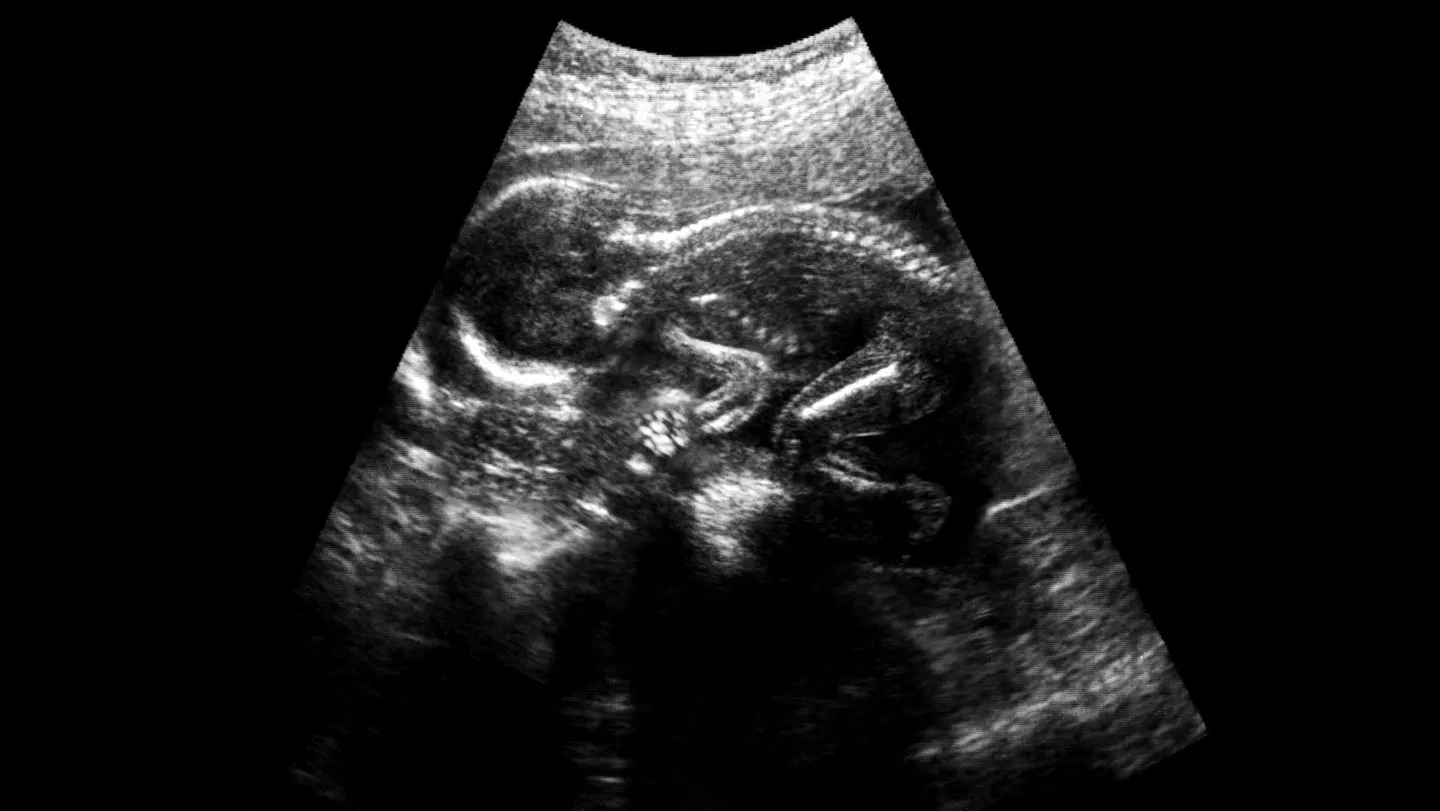

Des recherches récentes suggèrent que la chirurgie prénatale pour traiter la spina bifida pourrait être améliorée grâce à l’utilisation de cellules souches. Cette condition congénitale, qui affecte le développement de la moelle épinière, peut entraîner des complications graves, allant de problèmes moteurs à des difficultés cognitives.

La chirurgie prénatale, réalisée avant la naissance, a déjà prouvé son efficacité en réduisant les complications liées à la spina bifida. Cependant, l’incorporation de cellules souches dans ces procédures pourrait offrir de nouvelles perspectives pour améliorer les résultats cliniques. Les cellules souches ont la capacité de se différencier en divers types de cellules, ce qui pourrait favoriser la régénération des tissus endommagés.